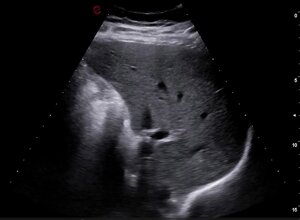

ECOGRAFIA ADDOME